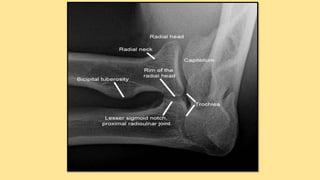

Osteology There are threebones that comprise the elbow joint: 1. The humerus 2. The radius 3. The ulna.

These bones giverise to 02 joints: HUMEROULNAR JOINT is the joint between the pulley like trochlea on the medial aspect of the distal of the humerus and the trochlear notch on the ulna. Humeroradial joint is the joint between the capitulum on the lateral aspect of the distal end of the humerus with the head of the radius. The humeroulnar and the humeroradial joints are the joints that give the elbow its characteristic hinge like

The PROXIMAL RADIOULNARJOINT is the articulation between the circumferential head of the radius and a fibro- osseous ring formed by the radial groove of the ulna and the annular ligament that hold the head of the radius in this groove. The proximal radioulnar joint is functionally a PIVOT JOINT, allowing a rotational movement of the radius on the ulna.